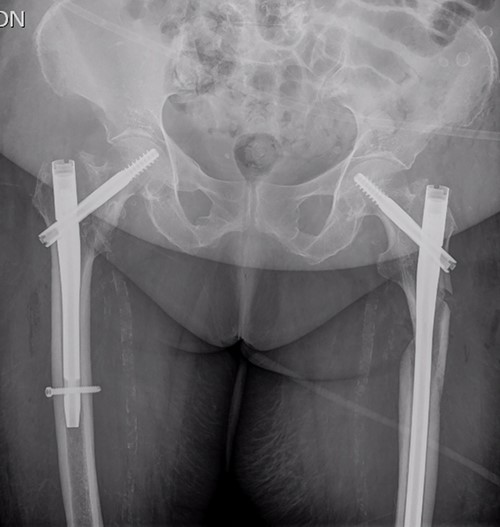

The postoperative course was satisfactory, without medical problems apart from non-complicated anemia (Hb 7.9 g/dl), solved with two units of red blood. On the first postoperative day, a radiographic control was completed (Fig. 3) and started early ambulation assisted by physiotherapists. On day twelve, she was transferred to a rehabilitation hospital. Outpatient follow-up visits evolving reasonably well. In the 6-month and 1-year check-up, the consolidation of the fracture was observed in the radiographic study (Fig. 4). No surgical wound problems, infections, or limping were identified. Anti-osteoporotic drug treatment was implemented along with an emphasis on a healthy diet with adequate protein intake and supplementation with calcium and vitamin D.

Postoperative anteroposterior pelvis radiograph: The left subtrochanteric fracture was first reduced with percutaneous assistance and synthesized with a reamed intramedullary long Gamma3 nail (340 mm,125°, Stryker®) with cephalic dynamic locking screw and two static distal locking screws. Then, after closed reduction, the right intertrochanteric fracture was fixated with a non-reamed short Gamma3 nail (180 mm,125°, Stryker®) with cephalic and distal dynamic locking screws.